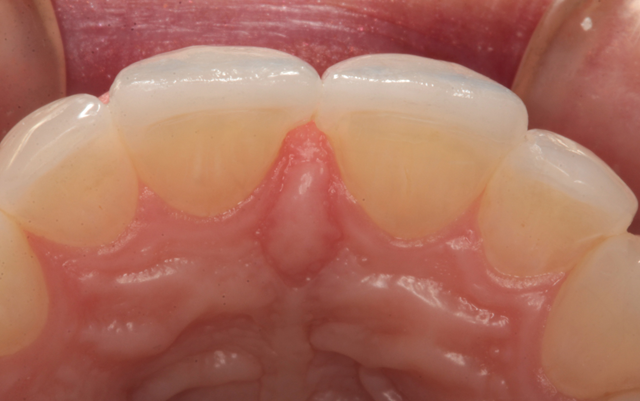

A preoperative impression was taken using Silginat alginate alternative impression material by Kettenbach. The previous laminates were carefully removed using a fine diamond bur (Brasseler) in a high speed handpiece with water spray. The prepared teeth can be seen from the facial view in Figure 4. The incisal view of the prepared teeth is shown in Figure 5. All prepared surfaces were in enamel.

Fig. 4 Fig. 5